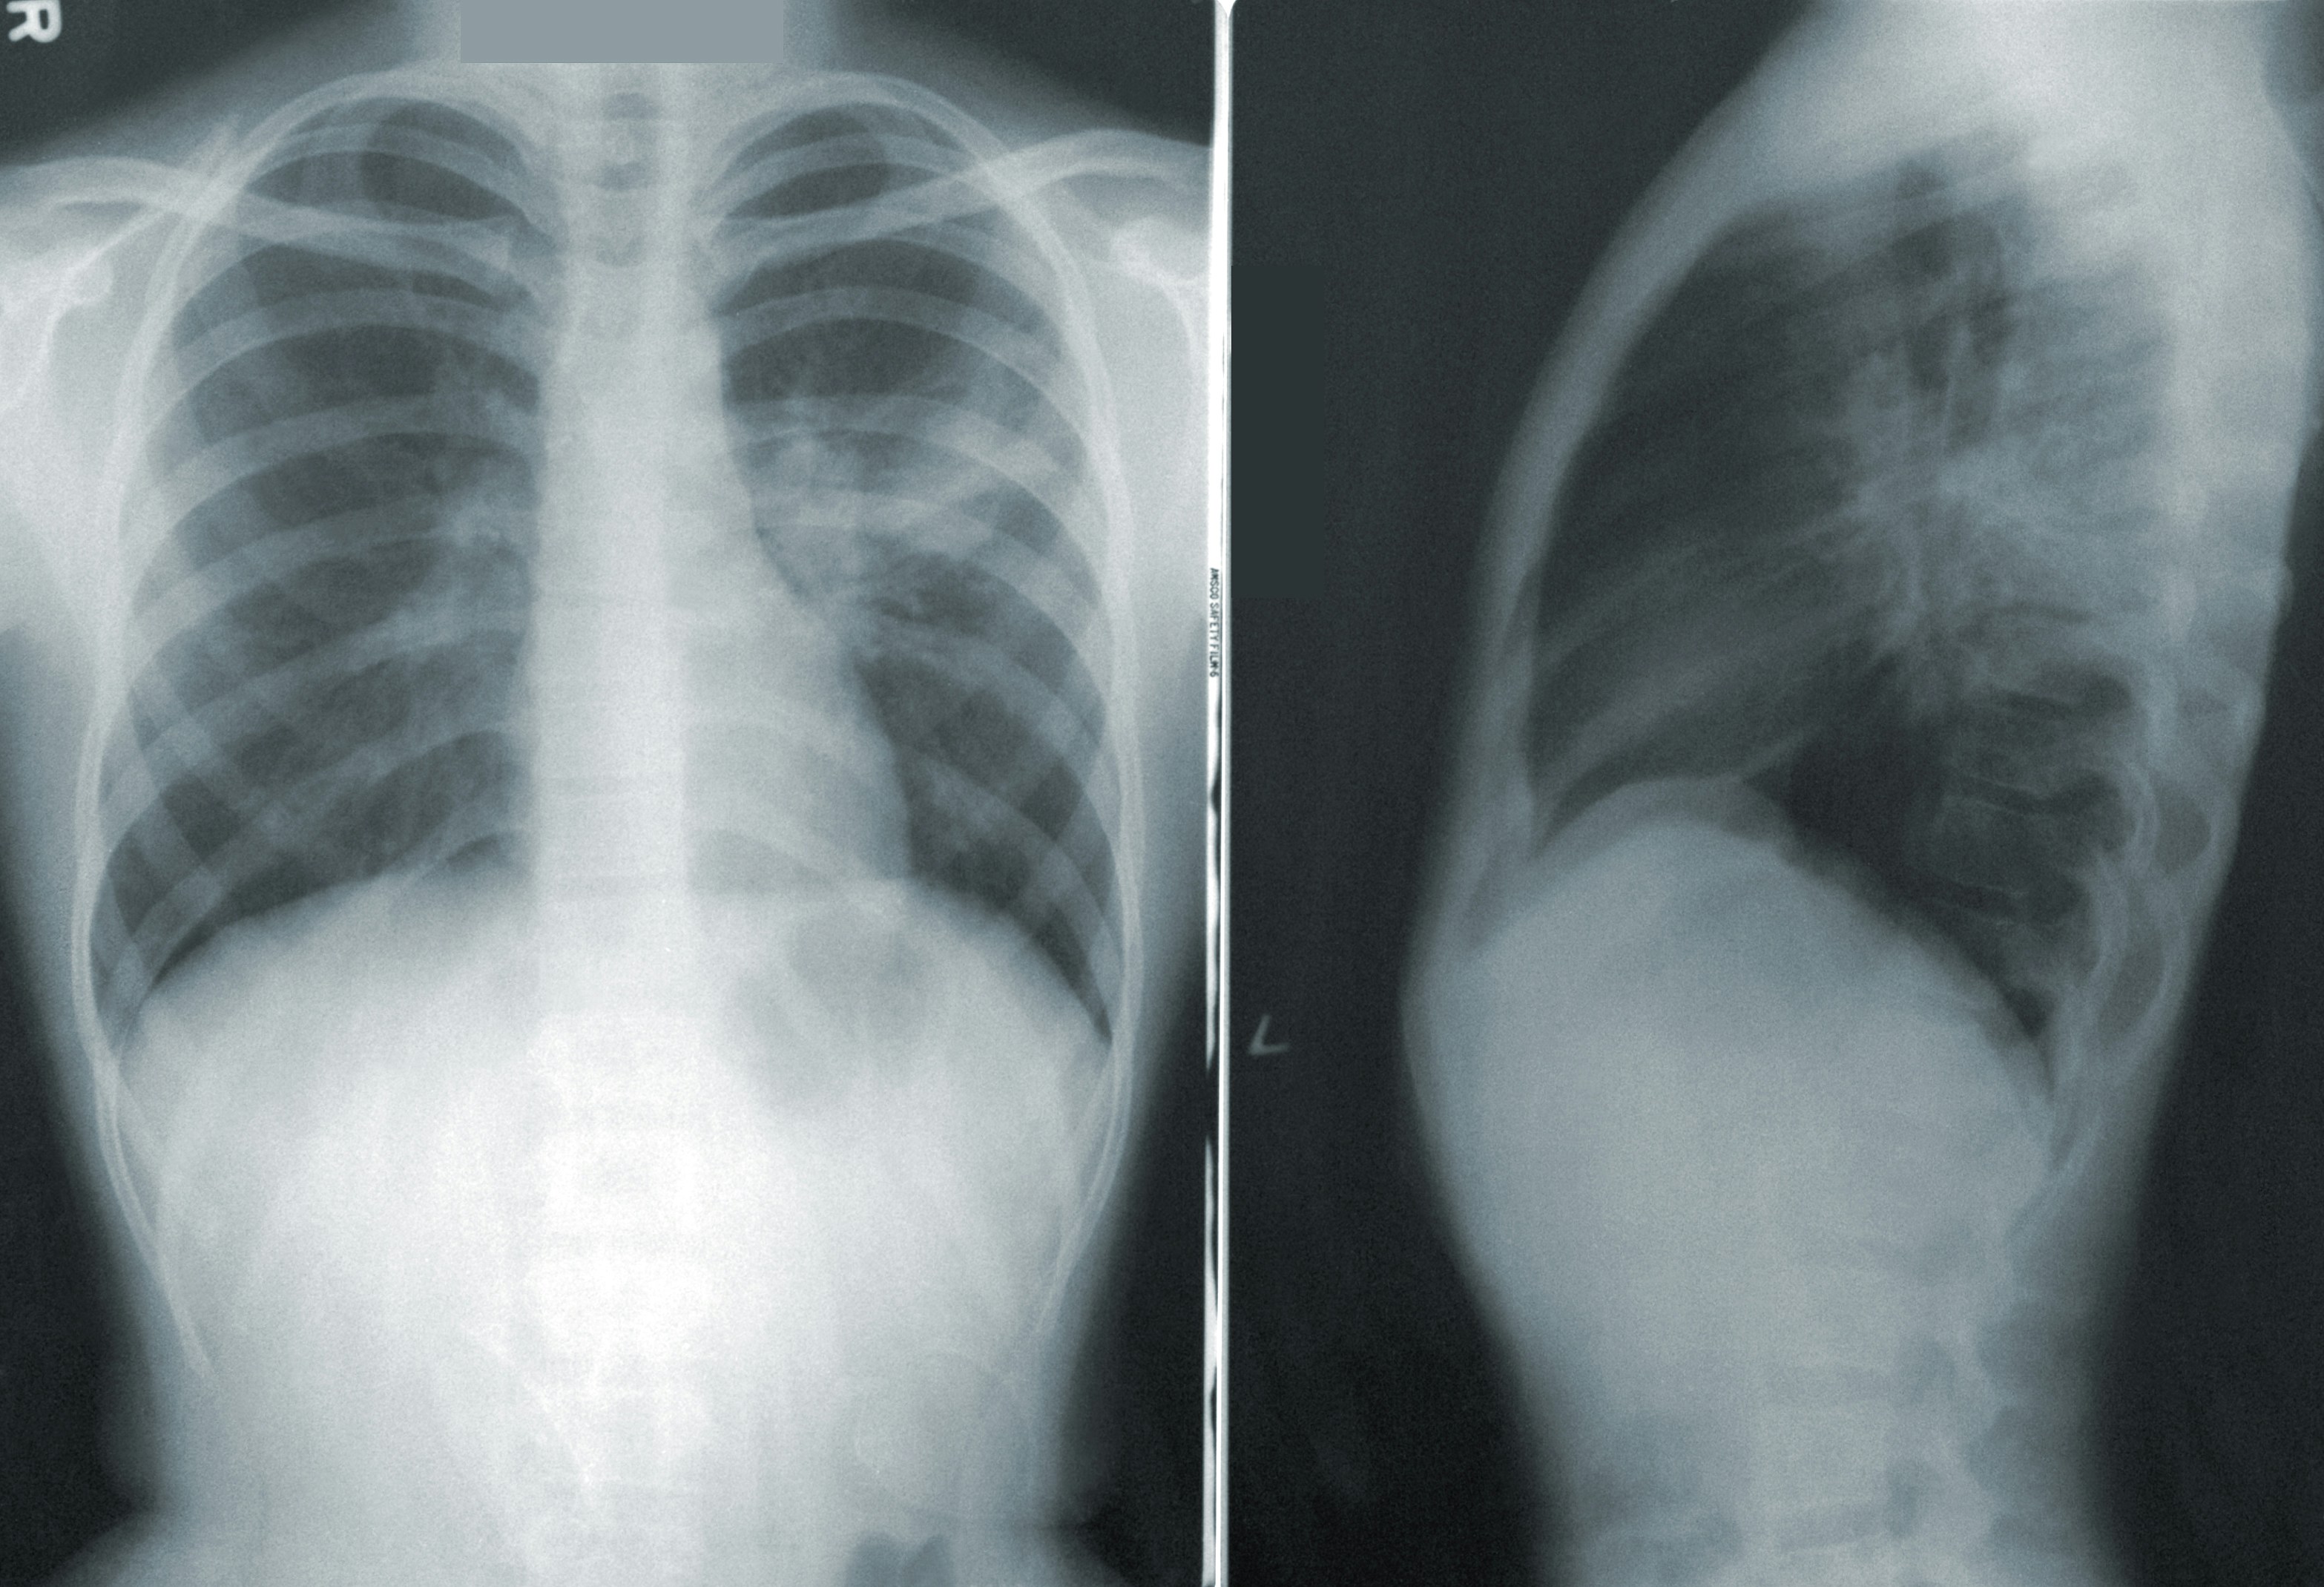

medical imaging

AI in medical imaging

Machine learning approaches accelerating pharmaceutical research and development.